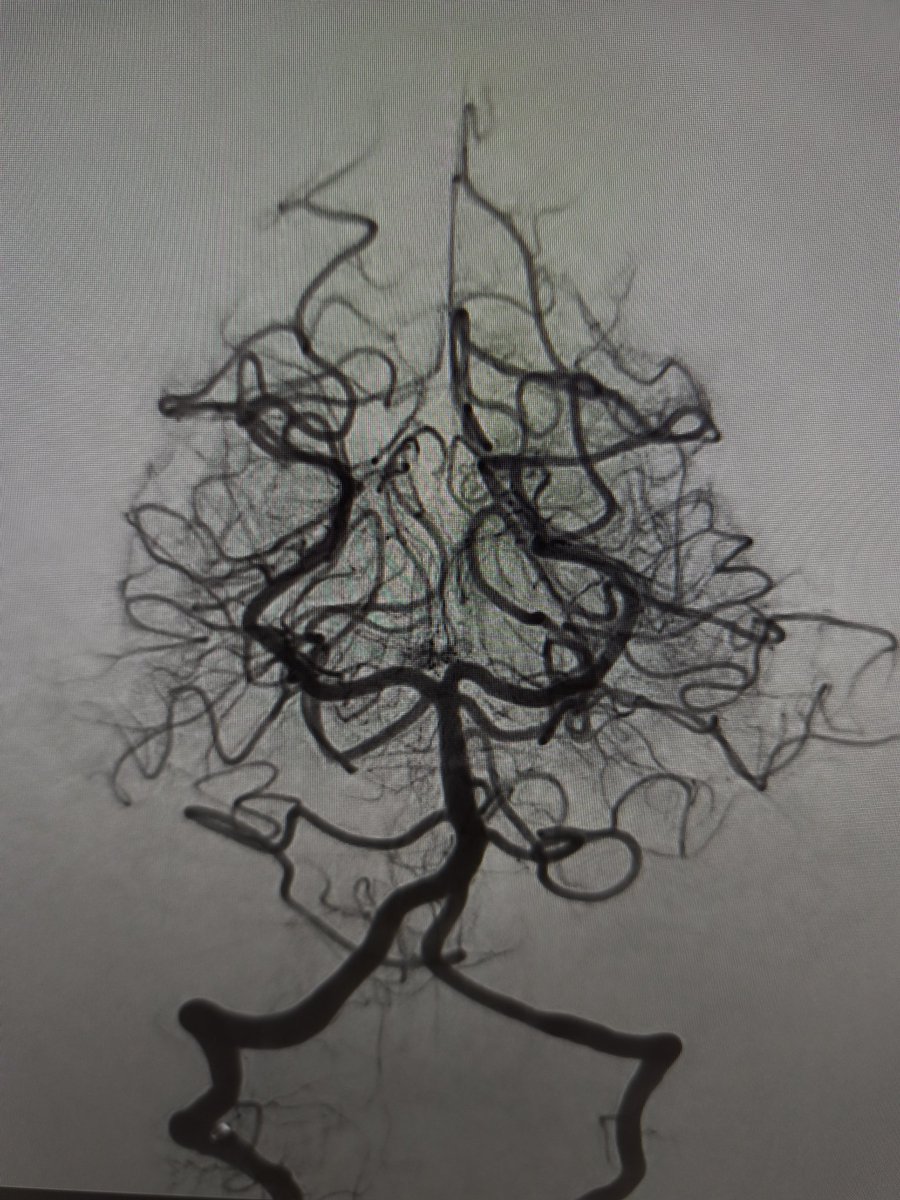

Ruptured cerebral arteriovenous malformation (#AVM), S&M grade IV

#Embolization + #Surgery

Complete Removal !!

Great team !!

Dr. Alberto Blanco (NSG)

Dr. Raquel Alcaraz (AN)

Dr. Raquel Tolos (AN)

Dr. Nerea Joshua (Neurophysiol)

@Sremollo

@IsaRCaamano

Rosa García-Sort (INR Nurse)